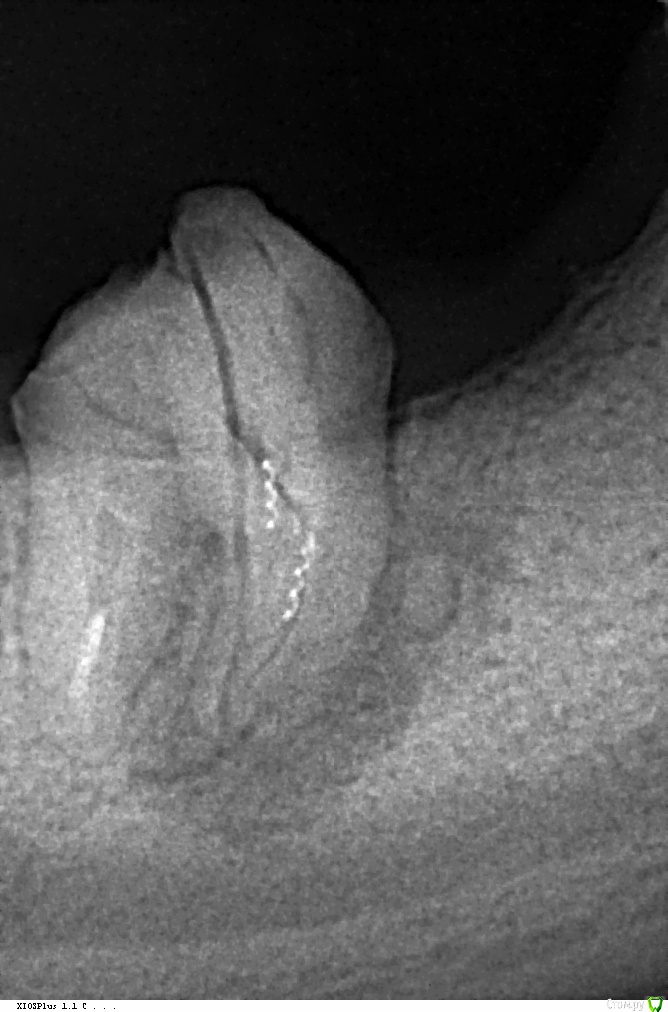

alex380 Опубликовано 16 января, 2016 Поделиться Опубликовано 16 января, 2016 Доброго дня, прошу совета !У меня долго стоял мост между 5 и 8, внизу справа, 6 и 7 нет. Мост отклеился, пошел ставить назад, оказалось, что 8-ка печально выглядит. Не хочется терять зуб и ставить имплант, прилагаю снимки, посоветуйте, стоит ли пытаться вылечить 8-ку, или однозначно рвать, и ставить 2 импланта ? И если удалять, то что делать дальше ? Ссылка на комментарий

alex380 Опубликовано 18 января, 2016 Автор Поделиться Опубликовано 18 января, 2016 выложите панорамный снимок (ОПТГ)Вот, сделал снимок. Пора обсуждать имплантацию, что ставить, где и у кого делать, и сколько будет стоить. Ссылка на комментарий